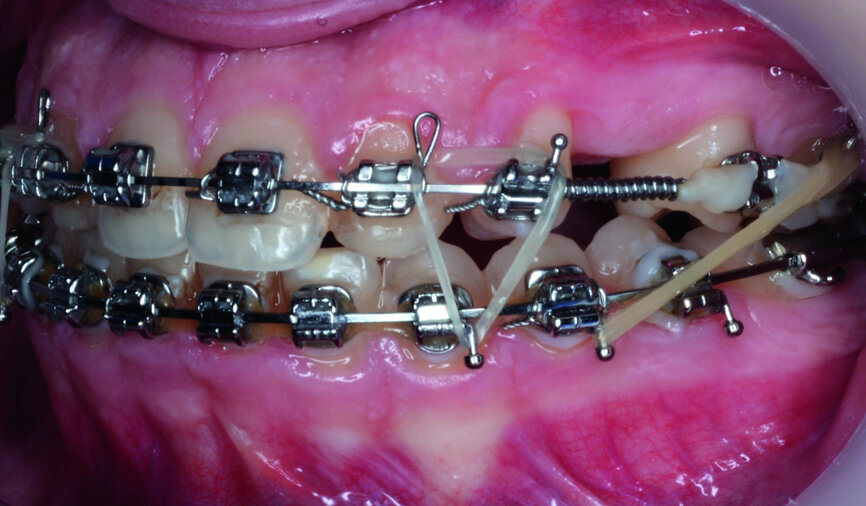

- Implants space opening: substitute laterals with canines (Figs. 23–25) and substitute canines with first premolars (Figs. 26–28).

- Finishing and occlusal settling (Figs. 29–31).

- Verifying the implant site width (Fig. 32) and provisory implants and crowns placement (Fig. 33).